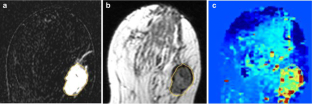

Fig. 1